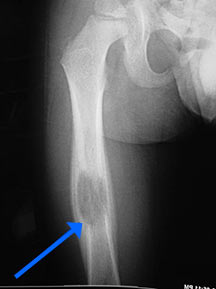

Radiographic imaging is used to help form a diagnosis. These include X-Ray, MRI, CT and Bone Scans

An example of an Eosinophilic Granuloma MRI is shown.